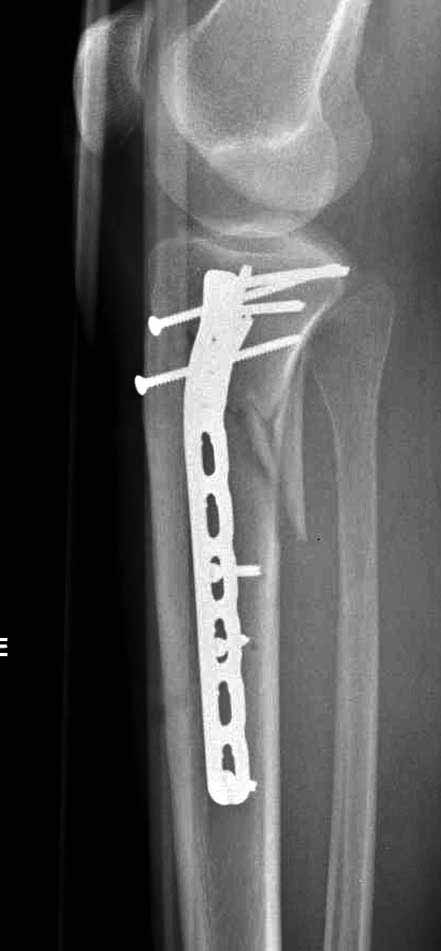

Двухколоннный перелом тибиал плато с вовлечением проксимального диафиза. Внутрисуставной компонент без смещения, и такой перелом можно лечить любым из описанных методов, о которых говорят наши коллеги.

Удобно аппаратом Илизарова или интрамедуллярным гвоздем. Гвозди не так сложно, как пугают, тем более Александр готов помощь с методичкой. Сперва надо установить компрессирующие шурупы на мыщелки. Давно отказались в пользу 3.5-4.0 мм кортикальных вместо толстых спонгиозных, потому что не доказаны преимущества толстых шурупов. Тонкие шурупы в субхондральной зоне смотрятся намного элегантнее, чем толстые 6.5.

Это мероприятие превращает перелом в простой диафизарный, который легко можно фиксировать гвоздем. Шурупы надо установить сзади предполагаемого места введения гвоздя.

Как понял, аппарат Илизарова не рассматривается предпочтительным для фиксации методом, хотя на фоне отека было бы идеальным для данного перелома. Для пластины требуется идеальная кожа, иначе наличие “суперсовременных имплантов” не поможет, и могут развиться серьезные осложнения.

В основном пластины рассчитаны на латеральную поверхность, потому что с латеральной стороны больше мягкотканая подушка, а также через латеральную колонну проходит ось конечности, что немаловажно в удержании оси от деформации.

Для изолированных переломов медиального тибиал плато, фиксацию можно провести “медиальной пластиной”. Некоторые компании, например Smith & Nephew делают медиальные и медиально-задние пластины, но они мягкие, и легко можно создать нужный контур. Жесткость создается за счет фиксации жесткими пластинами, например экстра артикулярной пластиной для дистального плеча от Synthes. Медиальный доступ тоже не из легких, надо работать между pes and medial gastroc.

Частая ошибка, когда фиксацию двух колонного перелома проводят одиночной пластиной, т.е с одной стороны, и такая фиксация не удерживает, происходит вторичноое смещение. Необходимо нейтрализовать второй пластиной или дополнительным наружным фиксатором.

Если у вас, кроме пластины, нет другого альтернативного варианта, тогда, учитывая мягкотканые проблемы с наружной стороны, я бы рекомендовал операцию делать в два этапа. Преимущества, сперва репозиция и фиксация перелома с медиальной стороны, а затем, после улучшения состояния мягких тканей, зафиксировать с латеральной стороны. Современные пластины имеют латеральный Jig для перкутанных мини доступов.

В приложении этапы фиксации Both Column Fx и пластиной Synthes для плеча при переломе медиального мыщелка.

Был бы очень признателен Александру Челнокову за предоставление методички..... Коллеги, спасибо за советы... К сожалению томографа в больнице нет. Рассматривали вариант штифтования данного перелома, но большинство коллег против, да и опыта штифтования подобных переломов тоже нет. Если есть рентгенограммы заштифтованных подобных переломов, коллеги, выложите на обозрение, пожалуйста….Долго искали и все же остановили пока свой выбор на проксимальной медиальной большеберцовой пластине Numelock фирмы Страйкер.

Медиальная пластина - действительно один из вариантов, но прочность будет невелика, и вполне может быть достаточно один раз оступиться, чтобы появилась несостоятельность.

Аппарат в этом отношении гораздо надежнее. Веером 5-6 спиц с упорами встречно в проксимальный отломок, из них 3-4 в плотную субхондральную кость, да 3-4 стержня в дистальный, и даже раннюю нагрузку можно одобрить. А если через 6-8 недель на метадиафизарном уровне не будет видно уверенного прогресса, то аппарат можно будет заменить на внутрикостный фиксатор. К этому времени несмещенные переломы суставной поверхности уже срастутся.